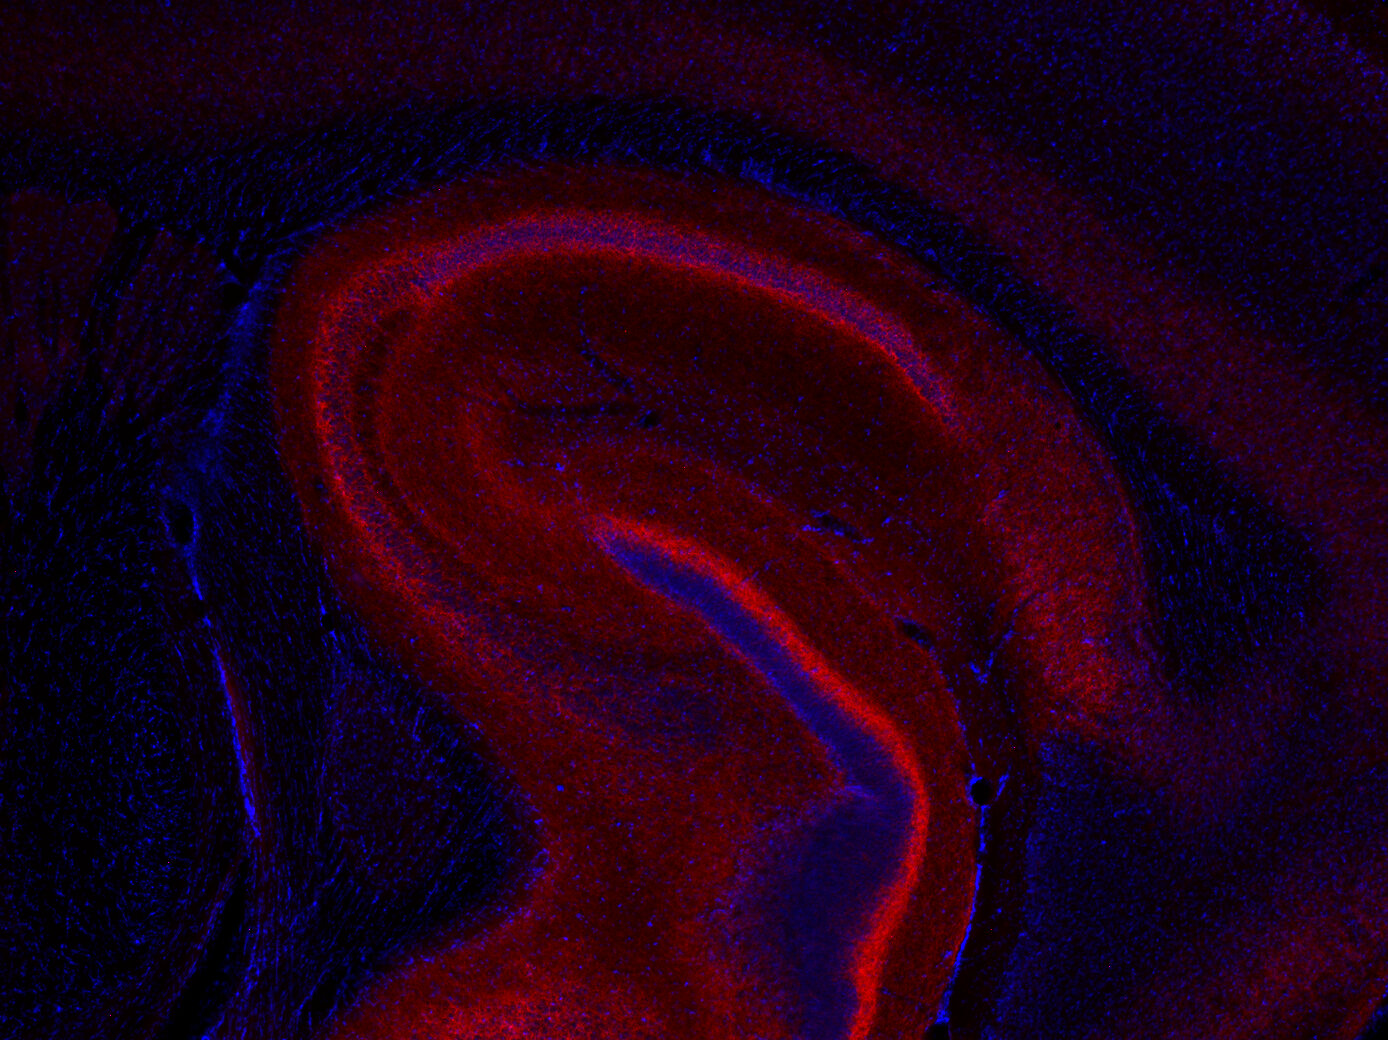

ICC: 1 : 500 gallery

IHC: 1 : 500 gallery

Immunohistochemistry (IHC) on 4% PFA perfusion fixed tissue with 24h PFA post fixation. Immunoreactivity is usually revealed by fluorescence or a chromogenic substrate. Some antibodies require special fixation methods or antigen retrieval steps. For details, please refer to the ”Remarks” section.